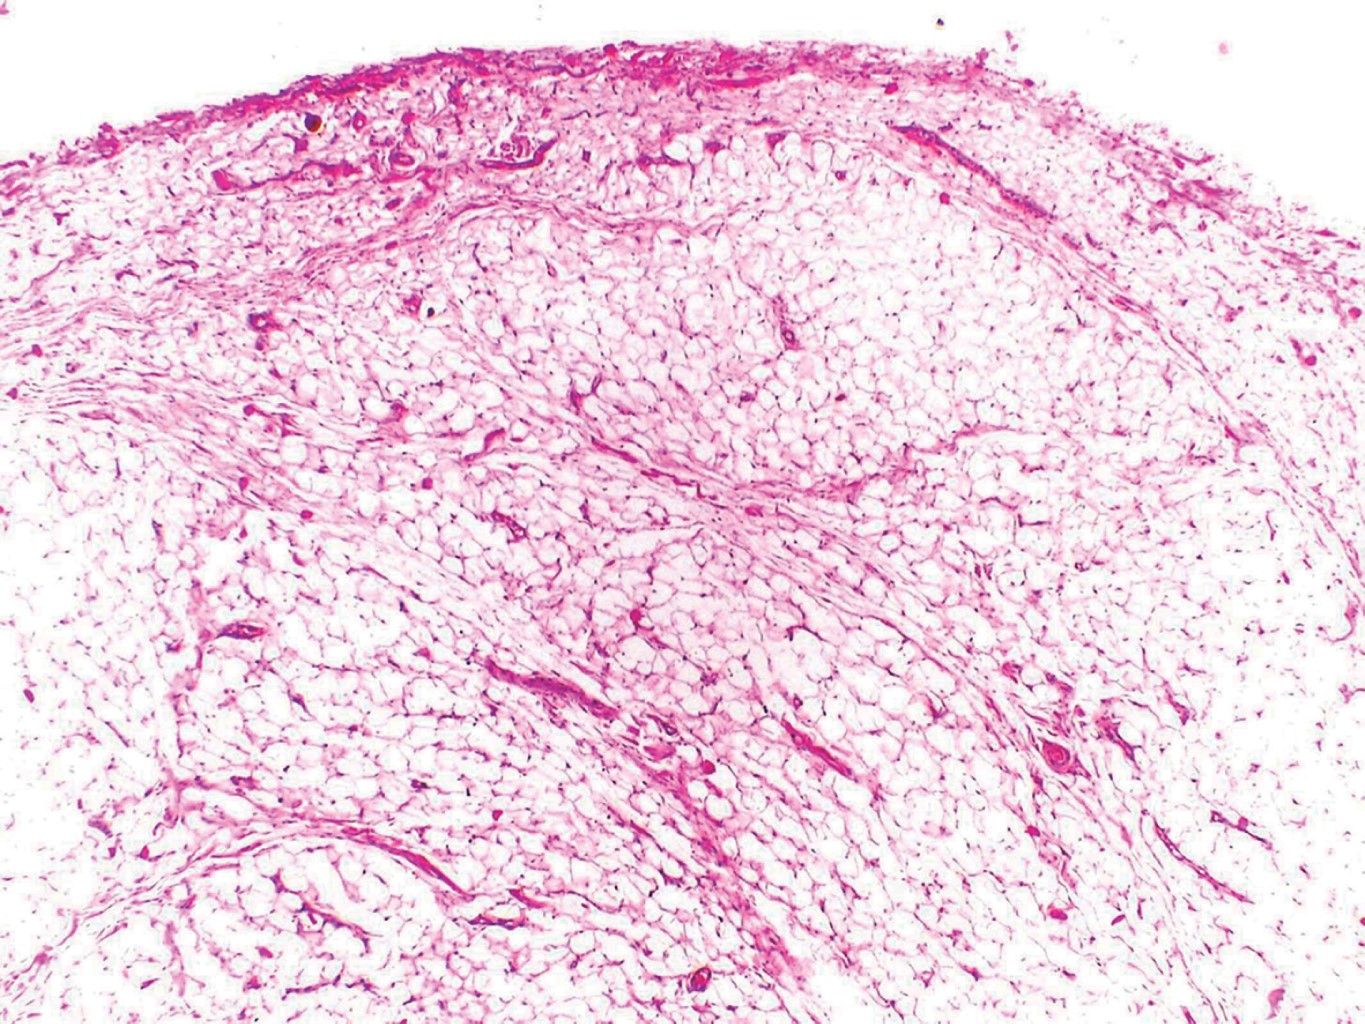

Con el diagnóstico presuntivo de lipoma en mucosa labial inferior, el paciente es referido al Servicio de Cirugía Dermatológica, en donde se realiza extirpación de la lesión con cierre directo (Figuras 2 y 3). El estudio histopatológico describe al corte la presencia de una neoformación bien circunscrita, constituida por numerosos adipocitos maduros de características normales, con algunos vasos dilatados y congestionados (Figuras 4, 5 y 6) confirmando con estos hallazgos el diagnóstico de lipoma. En el seguimiento postoperatorio del paciente únicamente se presenta cicatriz eutrófica; dos meses posteriores a la cirugía se da de alta.

Debido al lento crecimiento y evolución asintomática de estas neoformaciones, el diagnóstico suele retrasarse hasta que el tumor causa problemas funcionales o estéticos en los pacientes. Se calcula que el promedio de tiempo al momento de ser diagnosticado es de 2.6 años.5,7,8 El diagnóstico definitivo se establece mediante estudio histopatológico con tinción de rutina (hematoxilina y eosina), el cual muestra proliferación bien circunscrita de adipocitos maduros idénticos al tejido adiposo normal, aunque se ha reportado en algunos casos metaplasia cartilaginosa y ósea. En los lipomas intramusculares se pueden observar fibras de músculo estriado.9 Los lipomas, a diferencia del tejido adiposo normal, suelen estar bien circunscritos, en ocasiones encapsulados, pero sin vascularidad. Por otra parte, el tamaño de los adipocitos suele ser mayor en los lipomas, no obstante, la mayoría de las veces no es posible distinguir entre ambas entidades.10 En algunos casos puede haber hallazgos asociados a traumatismo o sobreinfección, como la presencia de infiltrado inflamatorio, necrosis o licuefacción grasa.4

Figura 4